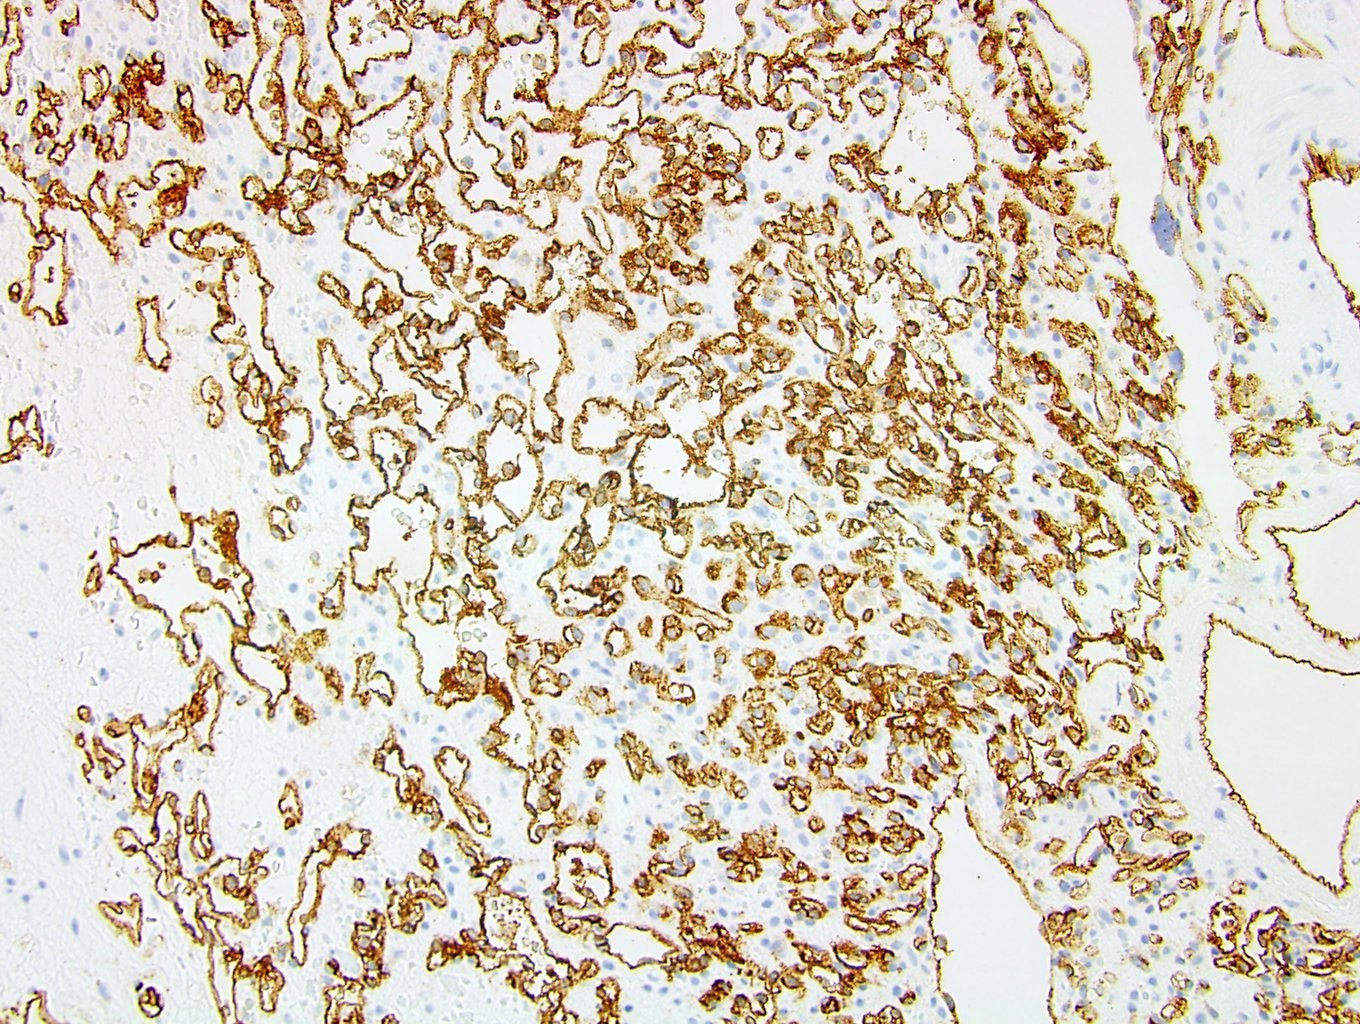

Positive stains

- Anastomosing hemangioma (1.3 cm) (see comment)

- Comment: The tumor is a well circumscribed, low grade vascular neoplasm composed of small capillary channels in an anastomosing pattern. There is no nuclear atypia or significant mitotic activity. In addition, foci of extramedullary hematopoiesis and fibrin thrombi are present. Immunohistochemistry is positive for CD31, supporting the diagnosis of a vascular neoplasm. The morphologic and immunohistochemical profile of the neoplasm is consistent with anastomosing hemangioma.

Differential diagnosis

- Lymphangioma:

- Positive for D2-40

- Renal cell carcinoma:

- Positive for PAX8, cytokeratins and CD10 (Arch Pathol Lab Med 2020;144:240)

- Angiosarcoma:

- Glomus tumor / glomangioma:

- Positive for smooth muscle actin, vimentin, collagen type IV and CD57 (Int J Surg Pathol 2011;19:393)

- Negative for vascular markers such as CD31, CD34, von Willebrand factor and WT1